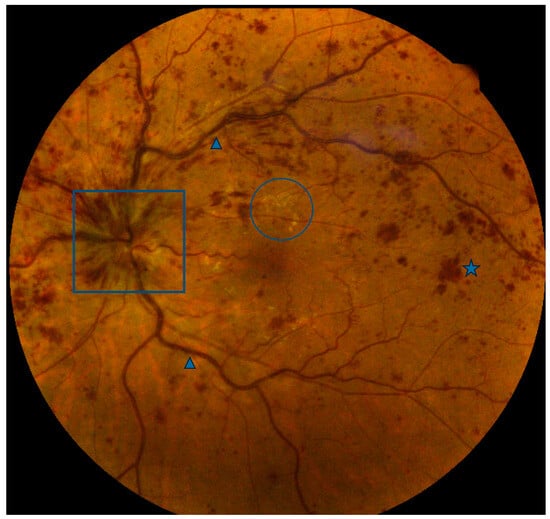

Figure 1.

Color fundus photo of a central retinal vein occlusion with optic disc edema (box), venous dilation and tortuosity (arrowheads), intraretinal hemorrhages (one of many, star), and exudates (one group of many, circle).

Due to this theorized mechanism, CRVO has been examined for its relationship to systemic cardiovascular disease. Hypertension, diabetes, and open-angle glaucoma all are risk factors for CRVO []. CRVO itself appears to increase the risk of incident cardiovascular disease by over 10% compared to an age-matched cohort []. Patients with any form of retinal vein occlusion have higher calculated cardiovascular risk (cCVDR) scores as determined using the Framingham algorithm. In one study, the 10-year cCVDR for RVO patients was approximately 5% higher (20.6% versus 15.7%) than age-matched controls []. RVO also appears to increase the risk of myocardial infarction. A propensity score-matched and -adjusted study found that retinal vein occlusion patients had a modestly higher risk of acute MI (hazard ratio of 1.21; 95% CI: 1.13 to 1.30) compared to age-, sex-, and non-cardiovascular-comorbidity-matched control patients. Moreover, among all retinal vein occlusion patients, CRVO patients had a significantly higher occurrence rate of acute myocardial infarction than BRVO patients (3.6% versus 3.12%, (p < 0.0001)) []. Indeed, RVOs as a whole increase the risk of heart myocardial infarction and peripheral arterial disease by approximately 25% and increase the risk of congestive heart failure by approximately 50% in a recent cohort study meta-analysis [].